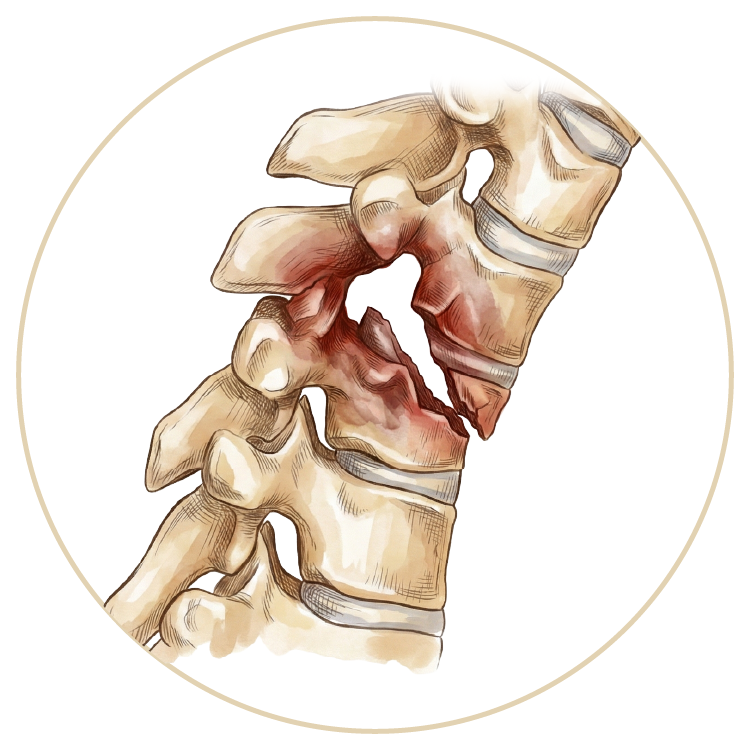

Omurga (Bel - Boyun - Sırt) Hastalıkları

OmurgaHastalıkları

Skolyoz